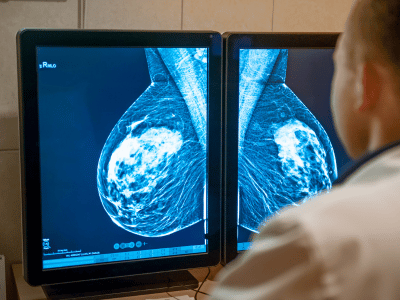

Há um grande desafio em diagnosticar mulheres jovens pela densidade das mamas, o que dificulta a realização do principal exame de detecção: a mamografia; outro desafio deve-se à negligência das próprias mulheres em subestimar o surgimento da doença e não fazerem checkups anuais.

Um nódulo ou qualquer outro sinal suspeito nas mamas deve ser investigado para confirmar se é ou não câncer de mama. Para uma melhor investigação, além do exame clínico das mamas (toque), exames de imagem podem ser solicitados: mamografia, ultrassom ou ressonância magnética (este em casos bem específicos).

A ultrassonografia é uma opção inicial para acompanhamento da sua saúde e, ao apontar anormalidades, podem ser solicitados outros exames para uma investigação mais precisa.